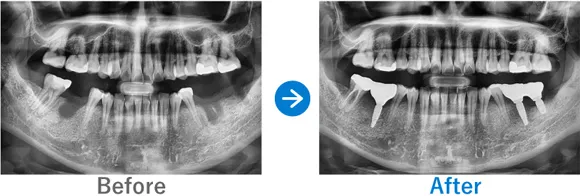

上の歯3本をインプラントに。骨が細くても骨補填によって施術可能

右上4・5が縦半分に破折し膿んでいる。左上5の歯根が短くぐらつきがある

インプラント3本:右上4・5、左上5

1,512,500円(内訳:抜歯ソケットプリザベーション、インプラント3本(ストローマン)、ガイド、仮歯、保証20年)

治療結果

上顎3本のインプラント治療を行いました。上顎の骨が細かったため、抜歯時に骨補填の抜歯ソケットプリザベーションを実施。これにより、インプラントを適切に埋入できました。しっかり噛めるようになり、喜んでいただけました。

噛む力が強いので、今後はブラキシズム(歯ぎしりや食いしばり)の対策が必要です。